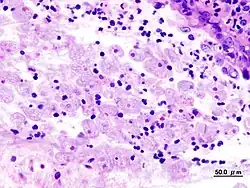

Biopsie du colon dans la dysenterie amibienne

Quand les examens parasitologiques sont négatifs, le sérodiagnostic et la rectoscopie sont des examens d'appoints. Le sérodiagnostic est négatif dans les dysenteries aigües, mais il tend à devenir positif par la suite.

La rectoscopie montre une muqueuse inflammatoire et hémorragique avec des ulcérations « en coup d'ongle ». La biopsie colique peut montrer en phase aigüe les microabcès « en bouton de chemise », et en cas d'amœbome, un granulome inflammatoire.